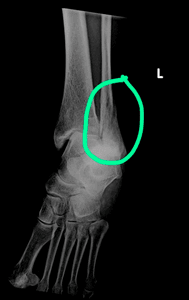

Por volta das 10h da manhã eu sofri um acidente bem sério ao subir a escada na casa do meu filho. Foi uma torção de tornozelo terrível.

E aí inicia uma grande luta: tornozelo torcido, rompimento de ligamentos e duas fraturas.  Uau!  Que dor!

Tive que ficar quase quinze dias de repouso após colocarem o tornozelo no lugar e passar quase dois dias no hospital. Não pude fazer a cirurgia logo em seguida e passei por cirurgia no dia 29 de junho para colocarem placas, pinos e restaurarem os ligamentos.